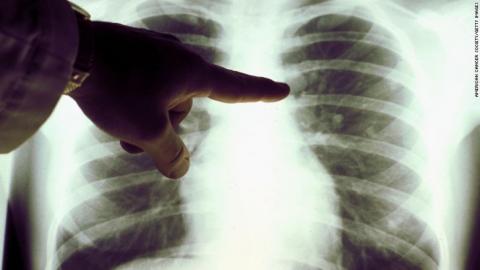

AMY GUTTMAN: Dr. Goggins monitors Phillips with regular scans.

DR. TIMOTHY GOGGINS: Compare this to where he is today, no evidence of growth necessarily in that area. In fact, there might even be shrinkage. I would have expected, in this case, further growth, definitely within the lungs. I’m surprised Mick’s still here.

So, I do believe that, outside of divine intervention, there’s some sort of scientific basis to what he’s doing.